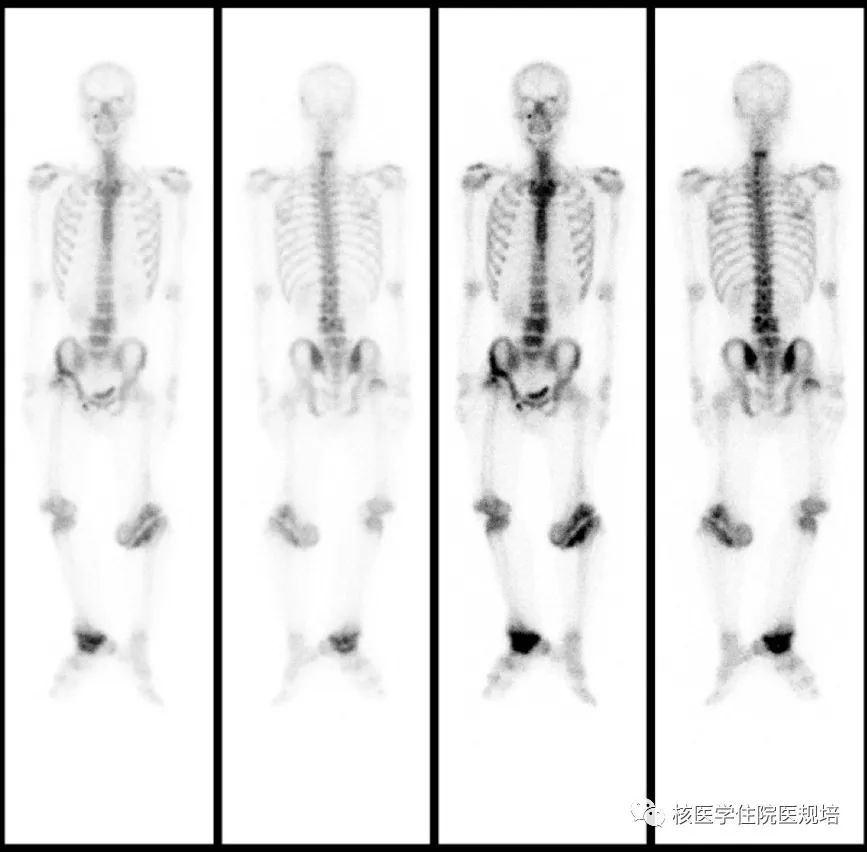

图6.

检查所见:

静脉注射99mTc-MDP 3~4小时后行全身前、后位平面显像。影像所见:全身骨骼显像清晰,脊柱形态欠规整,放射性分布不均匀,下位颈椎可见片状放射性浓聚灶,腰椎顺列不佳,L3、L4椎体似相互融合,放射性分布增高;右股骨头失常态,脱出髋臼向后上方移位;左膝关节及右踝关节对位不良,关节周围可见团片状不均匀放射性浓聚灶;右膝关节对位可,放射性分布增高;其余诸骨未见明显异常放射性分布。右耻骨下方点状放射性摄取为污染所致。

检查意见:

脊柱及多关节血运代谢增强灶,符合先天性无痛无汗症所致多发Charcot关节表现。